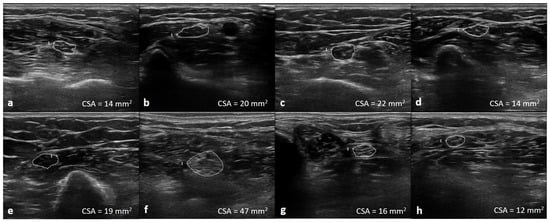

The UPSA was calculated as follows: median nerve CSA at the mid arm, elbow and forearm; ulnar nerve CSA at the mid arm and forearm; tibial nerve CSA at the popliteal fossa and ankle; and fibular nerve CSA at the lateral popliteal fossa (Figure 1). Each CSA value of the peripheral nerves at the anatomical locations described above was evaluated according to previous published boundary values [18]. Individual nerve enlargement >100% and <150% of the referenced upper limit of normal was scored 1, and individual nerve CSA >150% was scored 2. The maximum score was 16 (Supplementary Materials).

Figure 1. Illustration of the ultrasonographic nerve segments at median forearm (a), elbow (b), mid-arm (c); ulnar forearm (d), mid-arm (e); tibial knee (f), ankle (g); and fibular knee (h) of one of the CIDP patients. Total UPSA score: (2 + 2 + 2 + 2 + 2 + 2 + 1 + 1) = 14.